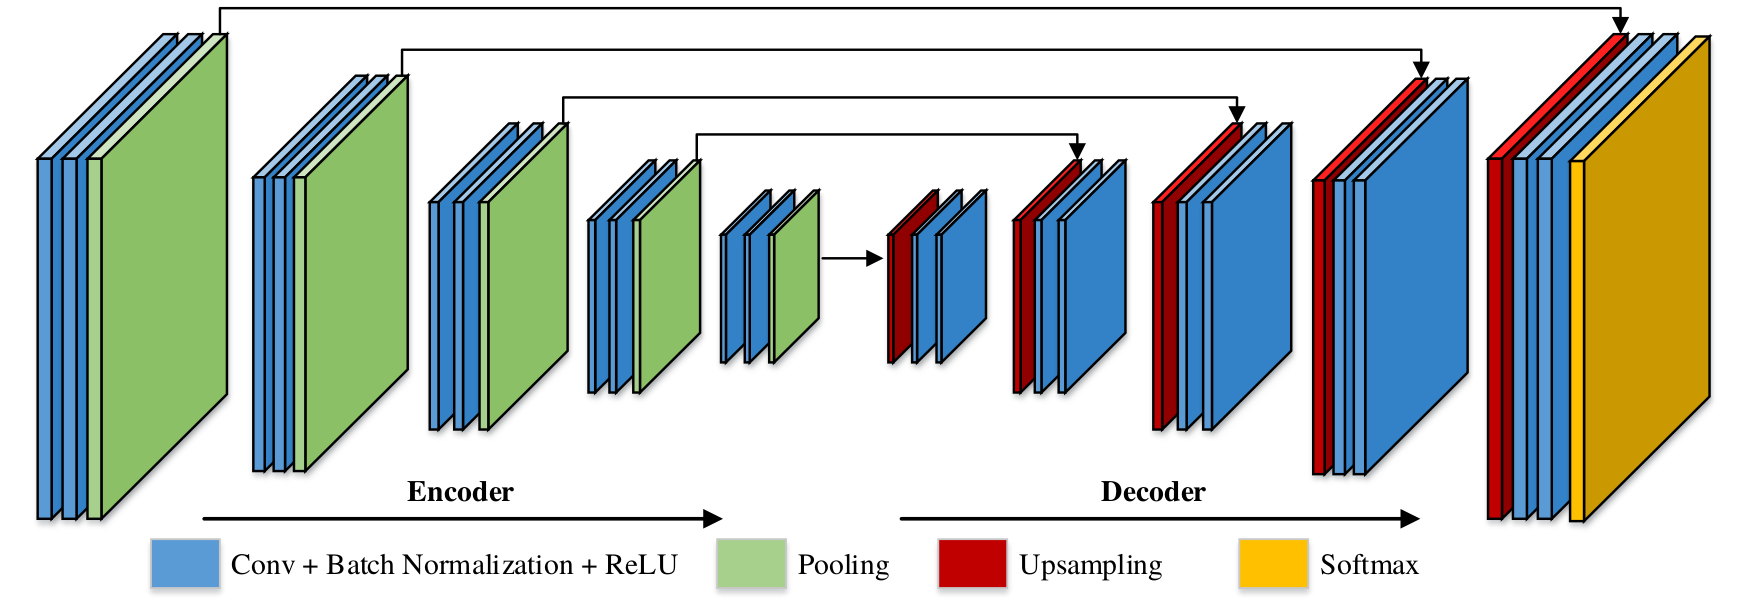

III-E Shenzhen Institute of Advanced Technology

Method 5 was from a team at the Shenzhen Institute of Advanced Technology (SIAT) consisting of Huoling Luo, Ahmed Elazab, Xingguang Duan, Chihua Fang, Qingmao Hu and Fucang Jia. They made use of the SegNet architecture [18] to address the challenge. This architecture is composed of a symmetric encoder-decoder structure where the output of the decoder is passed into a softmax classification layer (see Fig. 6). Following the original paper, a VGG16 encoder-decoder pretrained on ImageNet was used and fine-tuned on the challenge data. Models were trained for the binary and multi-label segmentation tasks, and the multi-label segmentation network is adapted for the type-segmentation task, by taking the weights from the parts segmentation data, modifying the number of outputs to equal the number of classes and fine-tuning this last layer.

The image aspect ratio was kept unchanged throughout training (via padding) however the images were resized to (480, 270) due to hardware limitations. To handle data imbalance between the instrument wrist and probe classes, a weight compensation strategy was used in the softmax layer:

| (1) |

where denotes the class weights, is the number of instrument part classes and is the prediction of class . Data augmentation of random flips and color, contrast and sharpness modifications were applied. Stochastic gradient descent was used to train the models with a learning rate of 0.001 and momentum of 0.9. Training time on an NVIDIA P100 GPU was 12 hours using a batch size of 4.